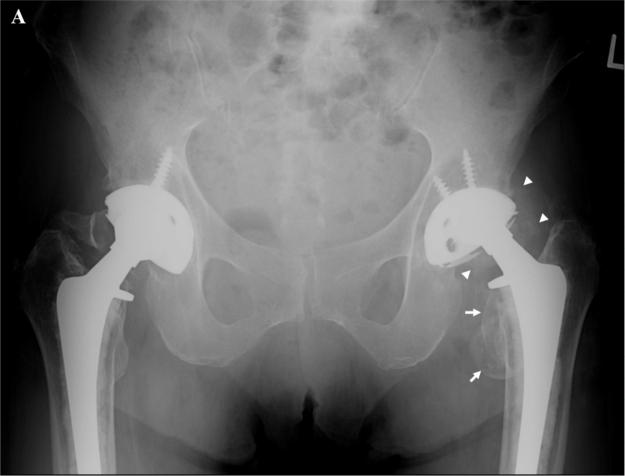

We present a case of an 85-year-old woman with extensive metallosis of the left hip joint secondary to prosthetic polyethelene liner dislocation and wear. Radiographs demonstrated amorphous cloudy radiodensities surrounding the prosthesis, a feature we have called the "cloud sign." The presence of amorphous cloudy radiodensities as a radiographic sign of metallosis has not been previously described to our knowledge.

我们报告一例85岁女性患者,因人工聚乙烯内衬脱位和磨损继发左髋关节广泛金属沉着症。X线片显示假体周围有无定形云雾状放射密度影,我们将这一特征称为“云雾征”。据我们所知,此前尚无将无定形云雾状放射密度影作为金属沉着症的影像学征象的相关描述。